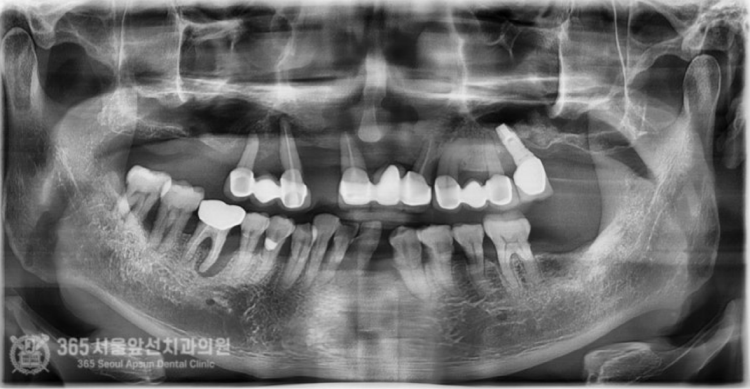

안녕하세요. 간석동치과 365서울앞선치과의원입니다. 과거에 타병원에서 임플란트 치료를 받으셨으나 뼈이식에 실패하여 고생하시다가 결국 치료를 포기하셨던 환자분의 치료 증례를 살펴보겠습니다. 치아들의 상태가 전반적으로 좋지 않아보입니다 ㅠㅠ 이번 기회에 전체적으로 치료 받길 원하셔서 성심성의껏 치료해드렸던 기억이 나네요 ㅎㅎ 촬영일시: 2024.06.14. 처음 내원 당시 엑스레이 사진입니다. 전체적으로 잇몸병이 산불번지듯 번지고 있어서 식사가 매우 불편하셨습니다. 특히 사진상 우측(실제 구강내에선 좌측에 해당하는 부위) 부위에 과거에 상악동 골이식술을 시행한 흔적이 관찰됩니다. 추후 설명드리겠으나, 과거에 타원에서 시행한 상악동 골이식술이 실패하여 이식재는 해당자리에 위치하고 있으나 뼈가 되어 있지 않았습니다.